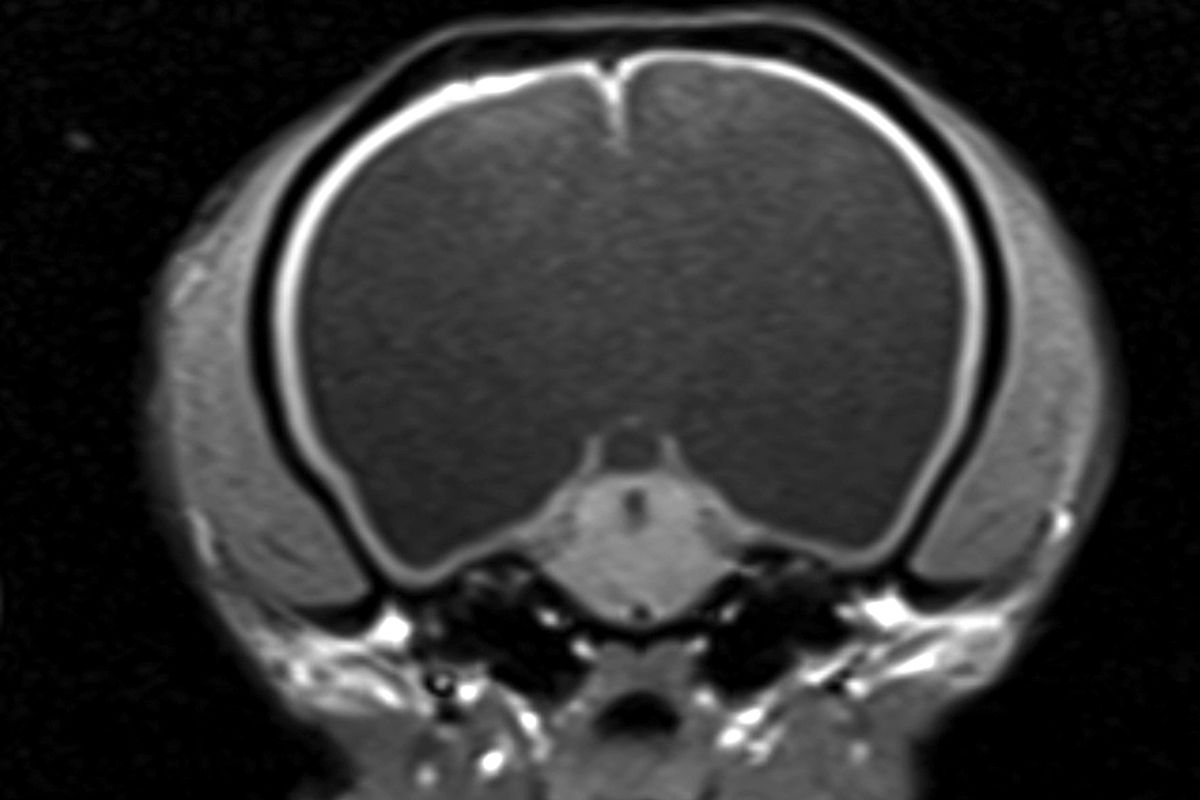

L’hydrocéphalie peut être la conséquence d’anomalies congénitales ou de lésions acquises telles que des tumeurs ou des maladies inflammatoires. Le site d’obstruction influe sur la partie du système ventriculaire qui s’hypertrophie, la dilatation survenant généralement en amont de l’obstruction. Par exemple, une obstruction au niveau du troisième ventricule entraîne une dilatation des deux ventricules latéraux mais pas du quatrième ventricule. L’hydrocéphalie commence par léser l’épithélium épendymaire des ventricules, ce qui permet à l’eau et à de grosses molécules de s’infiltrer dans la substance blanche adjacente, provoquant ainsi un œdème périventriculaire. La dilatation progressive des ventricules va comprimer la substance blanche, entraînant une démyélinisation et une dégénérescence axonale. Ceci peut conduire à une fenestration ou à une disparition complète du septum pellucidum séparant les ventricules latéraux, laissant place à un unique grand ventricule (Figure 1). La substance grise du cortex cérébral est initialement préservée et à ce stade, la mise en place chirurgicale d’une dérivation peut permettre une ré-expansion de la substance blanche et une régénération des axones restants. Dans les cas plus avancés, le cortex s’amincit, avec une vacuolisation et une destruction des neurones, et les lésions neuronales peuvent alors persister même après la dérivation ([2]). Lors d’obstruction aiguë, l’augmentation du volume de LCR peut être si rapide qu’elle entraîne une hypertension intracrânienne, altérant le flux sanguin vers le cerveau et provoquant davantage de lésions cérébrales.

Figure 1. IRM en coupe transversale pondérée en T1 au niveau du mésencéphale, montrant une hypertrophie sévère des ventricules latéraux et une disparition du septum pellucidum, laissant un espace unique rempli de LCR.© William B. Thomas